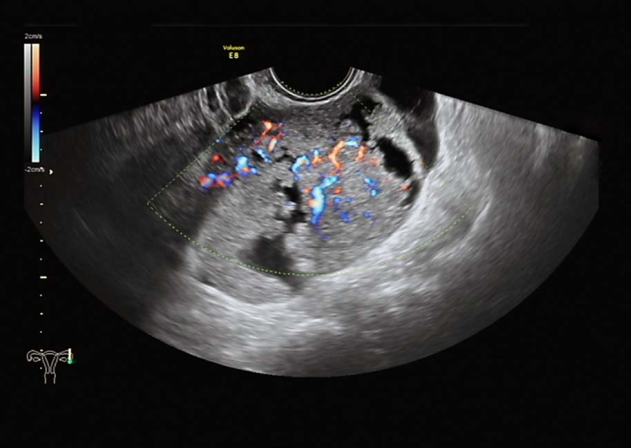

1.影像学检查 ①超声检查:可根据肿块的囊性或实性、囊内有无乳头等判断肿块性质,诊断符合率>90%。彩色多普勒超声扫描可测定肿块血流变化,有助于诊断。②磁共振、CT、PET检查:磁共振可较好判断肿块性质及其与周围器官的关系,有利于病灶定位及病灶与相邻结构关系的确定;CT可判断周围侵犯、淋巴结转移及远处转移情况;PET或PET-CT一般不推荐为初次诊断。

卵巢肿瘤超声检查

子宫水平位,如孕50天大小,内膜厚0.3cm,宫区内见多个低回声区,右卵巢3.0×2.7×2.4cm,部分囊性,内液清。左附件区见7.5×6.1×6.8cm囊实性包块,实性为主,边界尚清,周边可见部分卵巢组织,实性部分回声偏强,血流较丰富,能量多普勒提示实性部分血流丰富,RI=0.3。